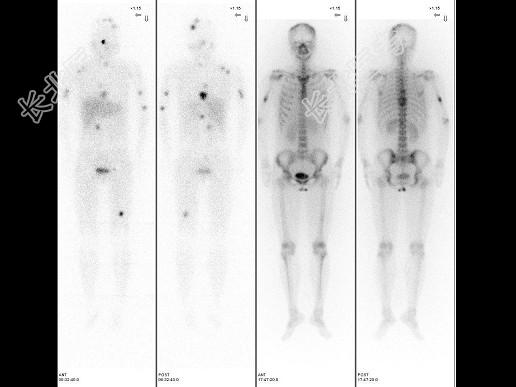

- [材料题] 女,22岁,阵发性高血压2年,间歇性头痛、胸背痛半年,CT示右肾门区占位病变,行¹³¹I-MIBG全身显像+局部X线定位及⁹⁹Tcᵐ-MDP骨显像如图